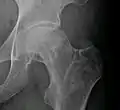

النخر اللاوعائي يؤثر بشكل كبير على نهايات (كردوس أو منطقة النشأ العظمي) العظام الطويلة مثل عظمة الفخذ (عظمة تمتد من مفصل الركبة حتى مفصل الورك). من المواقع الأخرى الشائعة العضد (عظم الذراع العلوي)، [17][18] الركبتين، [19][20] الكتفين، [17][18] الكاحلين والفك.[21] المرض قد يصيب عظمة واحدة فقط، أو عظام متعددة في نفس الوقت، أو عظام مختلفة في أوقات مختلفة.[22] النخر اللاوعائي عادة يصيب الأشخاص في السن بين 30 و 50 سنة، ونخر رأس عظمة الفخذ يصيب ما بين 10.000 إلى 20.000 شخص سنويا في الولايات المتحدة. عندما يصيب المرض رأس عظمة الفخذ في الأطفال، يؤدي إلى ما هو معروف بمتلازمة ليج-كالفي-بيرث.[23]

النخر اللاوعائي شائع بشكل خاص في مفصل الورك. هناك أساليب متعددة تستخدم لعلاج النخر اللاوعائي هذه الأيام، [22] الأسلوب الأكثر شيوعا هو استبدال الورك. ولكن هذا الأسلوب له العديد من الجوانب السلبية مثل طول الوقت اللازم للشفاء وقصر العمر المتوقع. لذلك فهو وسيلة فعالة للعلاج في المسنين، إلا ان الأطباء يخجلون من استخدامها في المرضى الأصغر سنا نظرا للأسباب المذكورة أعلاه. هناك وسيلة أخرى جديدة وواعدة وهي استبدال سطح مفصل الورك، أو الاستبدال بمعدن فوق معدن. وهي شكل من أشكال استبدال الورك، ولكن في هذا الإجراء يتم إزالة رأس عظمة الفخذ فقط على عكس عملية استبدال الورك التي يتم فيها إزالة كامل الرقبة. الاستبدال بمعدن فوق معدن لا تزال تجريبية في أمريكا لكنها أقرت في بريطانيا العظمى باعتبارها بديلا ممتازا لعملية استبدال الورك.إلا انها قد لا تكون مناسبة في جميع الحالات من النخر اللاوعائي، مدى ملاءمتها يعتمد على مقدار الضرر الذي وقع في رأس عظمة الفخذ للمريض. العظام تخضع باستمرار للتغيير أو إعادة التشكل.[24] يتم تكسير العظام بواسطة الخلايا الناقضة للعظم واعادة بنائها من قبل الخلايا البانية للعظام.[24] أيضا يصف بعض الأطباء بيسفوسفونايتس (على سبيل المثال أليندرونات) مما يقلل من معدل تكسير العظام بواسطة الخلايا الآكلة، وبالتالي منع الانهيار (وبالتحديد من الورك) بواسطة النخر اللاوعائي.[25]